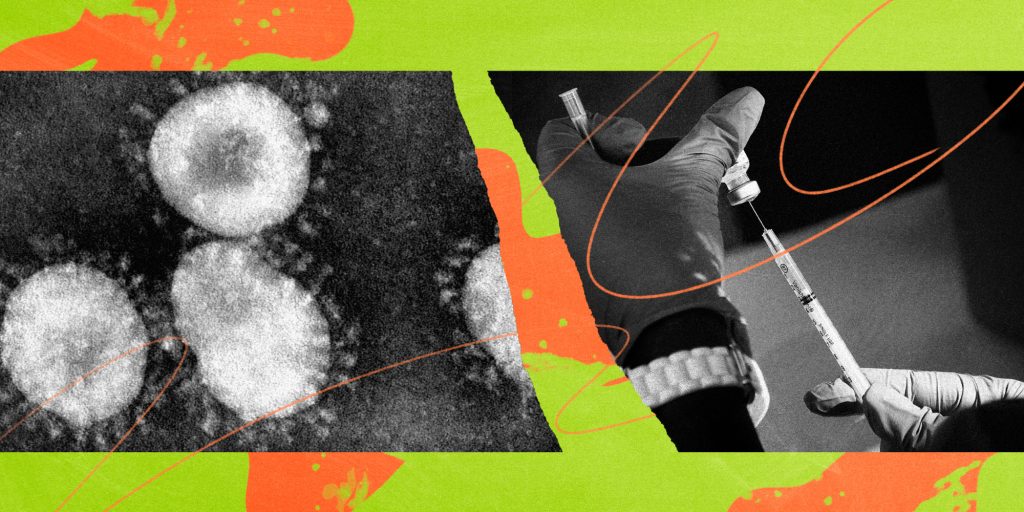

Varianti Delta, i identifikuar fillimisht në Indi, vijon “vrapin” nëpër botë dhe detyron një sërë shtetesh të rikthejnë kufizimet. Portugalia dhe Germania njoftojnë masa të reja sa i përket udhëtimeve në përpjekjen për të kufizuar përhapjen e variantit më të transmetueshëm të koronavirusit.

Nga e hëna, britanikët e pavaksinuar që udhëtojnë drejt Portugalisë do të karantinohen për dy javë, sipas një urdhri të qeverisë portugeze. Sipas rregullave të reja, çdokush që mbërrin në Portugali, nga ajri, toka apo deti do të duhet të provojë se është i vaksinuar plotësisht ose do të izolohet.

Masa ndërmerret pak pasi kancelarja Angela Merkel kritikoi Portugalinë, por edhe Greqinë javën e kaluar, pasi lejuan turistët britanikë të hynin në vend, ndërsa po qarkullonte varianti Delta. Portugalia u bë vendi i parë europian që njoftoi se varianti Delta ishte tanimë dominues në territorin e vet.

Gjermania kufizoi udhëtimet nga Portugalia dhe Rusia pasi Insituti Robert Koch i klasifikoi këto vende si zona me përhapje të varianteve shqetësuese. Masa do të hyjë në fuqi të hënën.

Rusia po përjeton një valë vdekjeprurëse infektimesh që besohet të jetë e nxitur nga mutacioni indian, me qindra të vdekur çdo ditë.

Në Sidnei të Australisë, në izolim që prej së dielës, infektimet me variantin indian shkojnë në 128. Raste janë regjistruar edhe në territorin verior, Kuinslend dhe Australinë Perëndimore.

Izraeli po përjeton gjithashtu rritje të rasteve pas një fushate të suksesshme vaksinimi. Kryeministri Naftali Benet ftoi të rinjtë të vaksinohen, në mënyrë që të shmanget rikthimi i kufizimeve. Të shqetësuara janë edhe autoritetet greke, pas evidentimit të rasteve të variantit Delta në ishullin e Kretës.